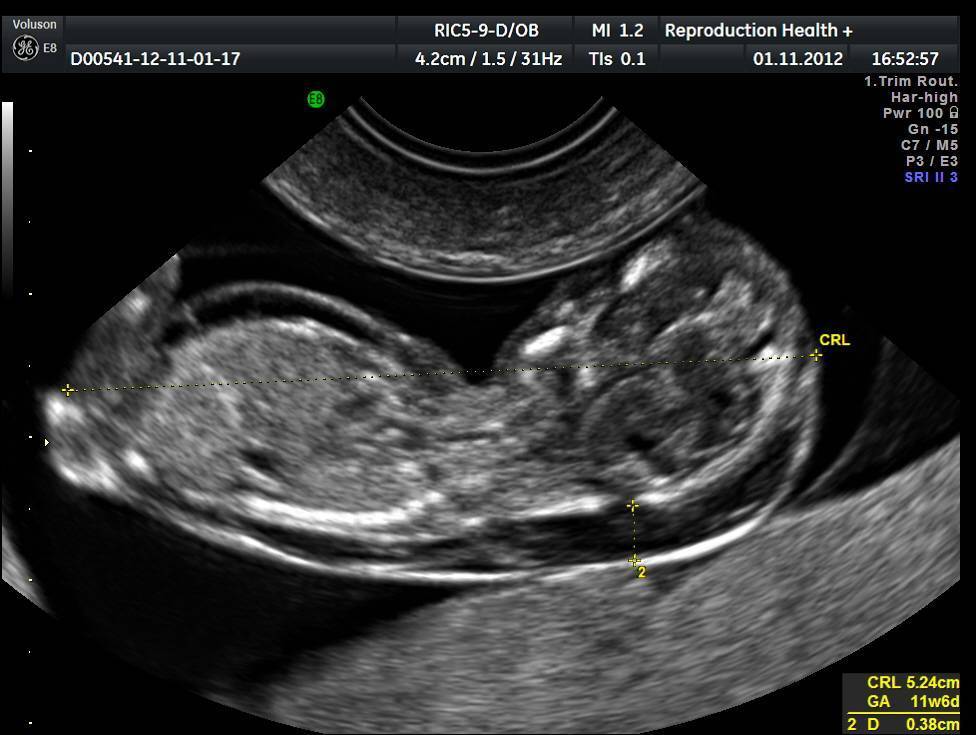

Первое УЗИ будущей маме назначают на 10–14 неделе беременности. Уже на этом сроке врачи делают первые выводы из своих наблюдений. Особо интересуют медиков размеры костей носа ребенка. Этот параметр позволяет сделать некоторые выводы об общем состоянии здоровья малыша.

12–13 акушерских недель – самый подходящий срок для того, чтобы впервые попытаться с помощью УЗИ визуализировать пропорции личика ребенка. Именно на этом этапе у деток обычно диагностируют гипоплазию носовых костей – один из ярчайших маркеров генетически обусловленных пороков развития плода.

Обнаружить гипоплазию носовой кости на начальных стадиях беременности могут помочь снимки, сделанные на ультразвуковом исследовании. Для изучения размеров эмбриона УЗИ начинают проводить на 10 неделе. Исследования позволяют увидеть объективное состояние развивающегося плода и наличие хромосомных аномалий.

На этом сроке очень важно присутствие самой носовой кости, размер которой можно определить дождавшись 12 недель. Последние модели аппаратов показывают повышенную точность данных

Полученные результаты помогают следить за развитием плода и дают возможность выявить какие-либо патологии.

Если у плода отсутствуют патологии, то необходимо как минимум 3 скрининговых исследования. УЗИ носовой кости можно выполнить при первом — на 10-14 неделе. Кроме этого обнаруживаются и грубые нарушения развития организма. Второе диагностическое ультразвуковое исследование выполняется на 20-24 неделе. Спектр диагностируемых патологий тут гораздо выше и могут быть обнаружены те пороки и нарушения, которые не были установлены при первом. Но стоит понимать, что если было пропущено первое УЗИ, то и некоторые заболевания могут быть упущены.